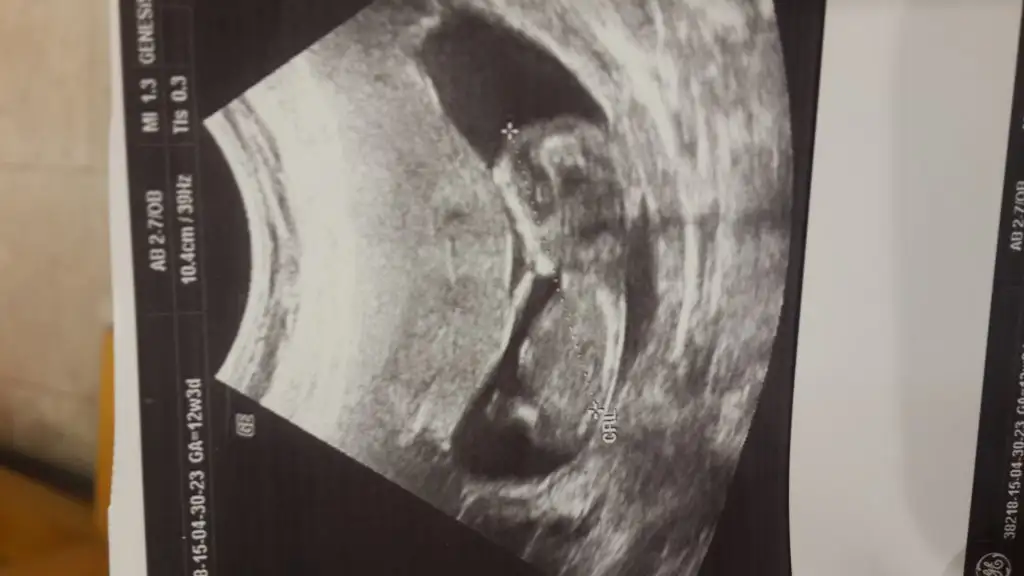

12+3 sizce cinsiyeti ne olabilor

Eklentiler

• 20150430_173607.webp

19 KB · Görüntüleme: 117

• 20150430_173617.webp

16,9 KB · Görüntüleme: 124